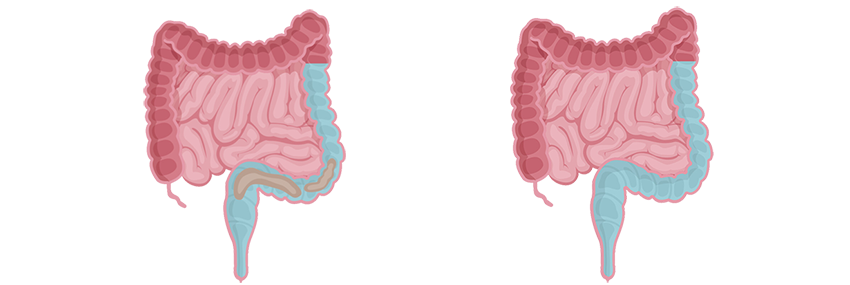

Darmspoelen is een gecontroleerde methode waarbij warm water via de anus in de dikke darm wordt ingebracht om de darmreflex te stimuleren en de darm te ledigen. Deze therapie kan leiden tot een aanzienlijke verbetering van klachten, zoals het verminderen van episodes van incontinentie en het voorkomen van obstipatie.

Darmspoelen of irrigeren is een kunstmatige manier om het rectum en/of deel van de dikke darm te ledigen door het inbrengen van water via het rectum, dit met behulp van een katheter of een conus. De katheter is voorzien van een opblaasbare ballon, de conus is kegelvormig. Het toegediende water veroorzaakt reflexmatige peristaltische

bewegingen die ervoor zorgen dat de ontlasting en het water worden uitgedreven zodra de katheter is verwijderd.

Hoe werkt Peristeen Plus?

- Er wordt een katheter in het rectum ingebracht.

- Via de katheter wordt water in het rectum en de dikke darm gebracht.

- De rectale katheter wordt verwijderd.

- Water en stoelgang kunnen worden afgevoerd.